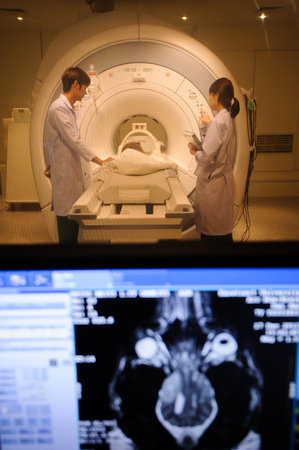

Radiographer performing diagnostic computed tomography on female patient

Close up of advanced mri equipment in a medical office analyzing brain scans and human health

A brain scan is shown on a screen while a patient undergoes a medical imaging procedure.

A state-of-the-art MRI machine in a high-tech medical imaging room with multiple screens displaying brain scans.